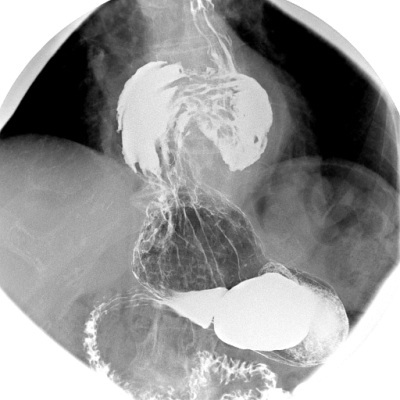

type of imaging

what is shown

ERCP - Endoscopic Retrograde Cholangiopancreatography + cholangiogram

normal bile duct diameter - rough guide

over the age of 30s

expect to be age in decades/10 as mm value

i.e. 40 → 4mm